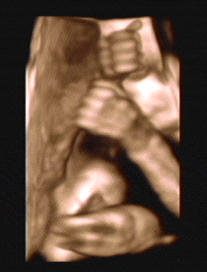

3D/4D SONOGRAPHY 18-24 WEEKS

- Normal Sonography is 2 dimensional. In 3 dimensional Sonography the information is obtained simultaneously in 3 planes (X, Y & Z).

- Highly sophisticated software reconstructs this information into a distinct 3D image.

- From a continuous 3D acquisition you get a live action view. It is known as 4D where 4th dimension is time.